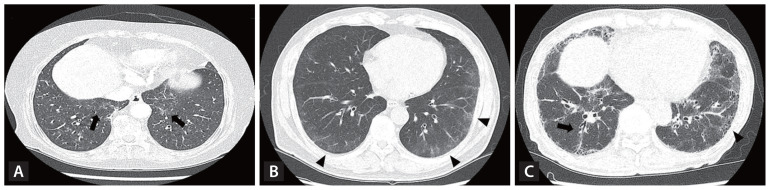

Interstitial lung abnormalities (ILAs) are early indicators of interstitial lung disease, often identified incidentally via computed tomography of the chest. This review explores the diagnostic criteria for ILAs as outlined by the Fleischner Society, highlights associated risk factors, examines their impact on patient outcomes, and discusses management strategies. The prevalence of ILAs varies significantly, ranging from 3% to 17% across populations. Key risk factors include advanced age, smoking status, and underlying genetic predispositions. Recent advancements in imaging analysis, particularly through automated quantitative systems, have enhanced the accuracy of ILA detection. Although often subtle in presentation, ILAs hold clinical significance due to their associations with impaired lung function, progressive fibrosis, and increased mortality. Therefore, monitoring and management plans should be individualized to the risk profile of patients. Further studies are needed to refine ILA diagnostic criteria, enhance our understanding of their clinical implications, and establish optimal timing for therapeutic interventions.